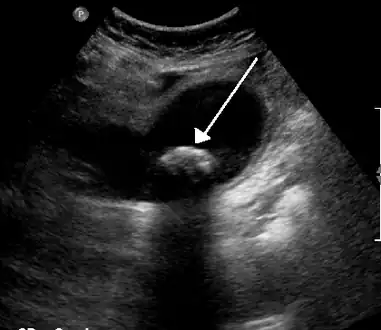

Biliary colic is often related to a stone in the gallbladder

Diagnosis is guided by the person's presenting symptoms and laboratory findings. The gold standard imaging modality for the presence of gallstones is ultrasound of the right upper quadrant. There are many reasons for this choice, including no exposure to radiation, low cost, and availability in city, urban, and rural hospitals. Gallstones are detected with a specificity and sensitivity of greater than 95% with ultrasound.[19] Further signs on ultrasound may suggest cholecystitis or choledocholithiasis.[13] Computed Tomography (CT) is not indicated when investigating for gallbladder disease as 60% of stones are not radiopaque.[13] CT should only be utilized if other intra-abdominal pathology exists or the diagnosis is uncertain.[20] Endoscopic retrograde cholangiopancreatography (ERCP) should be used only if lab tests suggest the existence of a gallstone in the bile duct.[13]